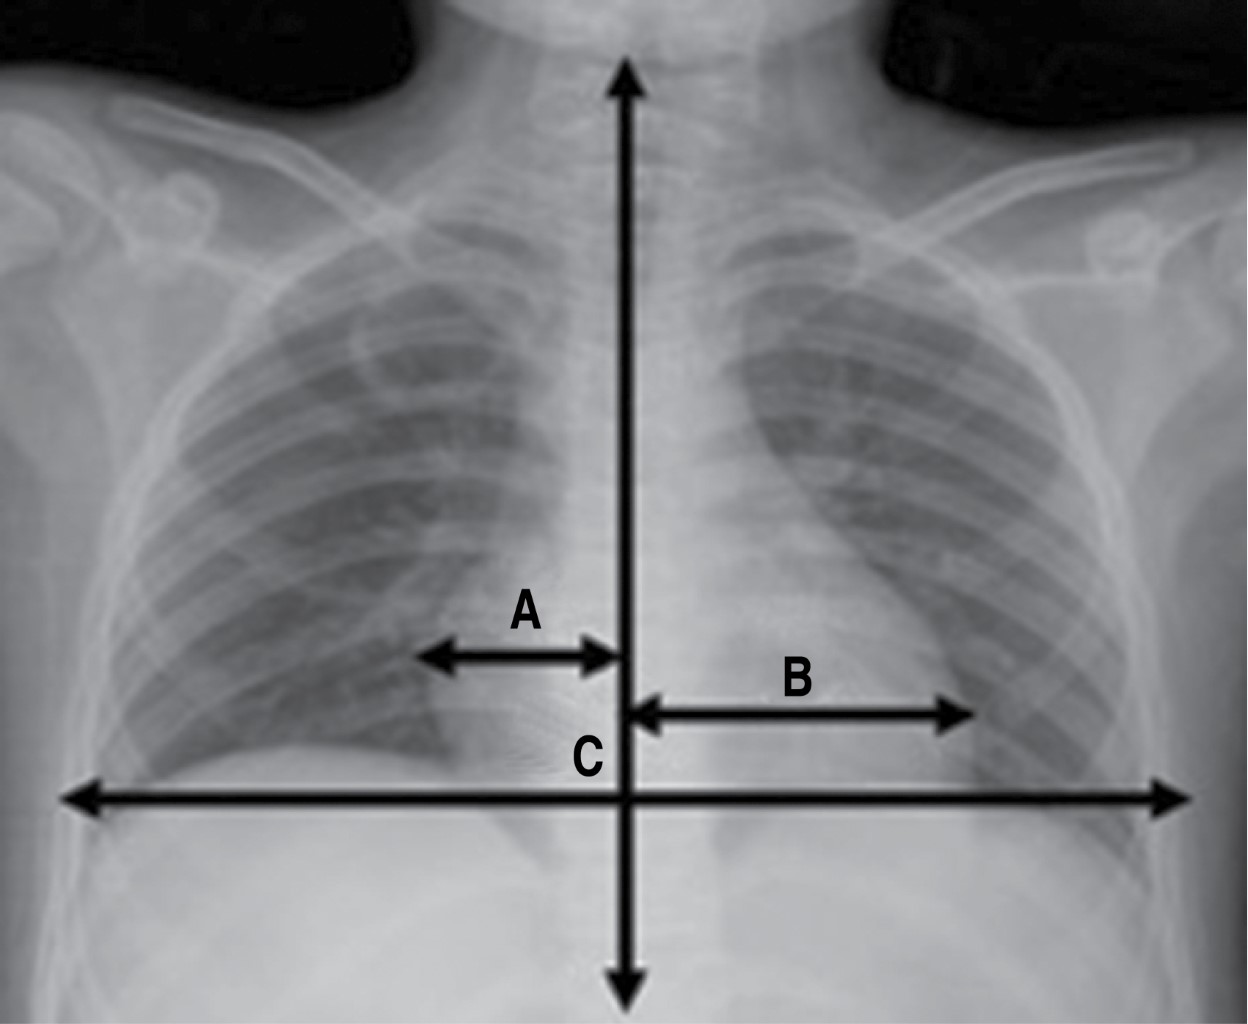

Tabla 1: Valores del índice cardiotorácico (CT) en las edades pediátricas.9-11 |

||

Edad |

Índice CT |

Rango |

0-3 semanas |

0.55 |

0.45-0.65 |

4-7 semanas |

0.58 |

0.46-0.70 |

1 año |

0.53 |

0.45-0.61 |

1 a 2 años |

0.49 |

0.39-0.60 |

2-6 años |

0.45 |

0.40-0.52 |

7 años |

< 0.50 |

0.40-0.50 |